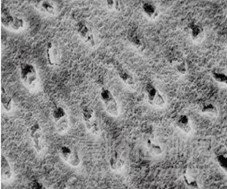

采用牙科用磷酸酸蝕劑對牙釉質(zhì)表面進(jìn)行酸蝕處理,可清除釉質(zhì)表面的涎液沉積物、菌斑及其他附著物,使表面羥基磷灰石礦物質(zhì)不均勻脫礦,形成凹凸不平的蜂窩狀表面結(jié)構(gòu),見圖1。這種結(jié)構(gòu)不但增加了粘接的表面積,而且能夠使粘接劑與釉質(zhì)間形成微機械嵌合作用,產(chǎn)生牢固的結(jié)合力。

圖1 牙釉質(zhì)表面酸蝕前后形態(tài)掃描電鏡圖示例

如圖1所示,(左)酸蝕前,正常的牙釉質(zhì)表面致密;(右)酸蝕后,表面不均勻脫礦,呈現(xiàn)蜂窩狀結(jié)構(gòu)。